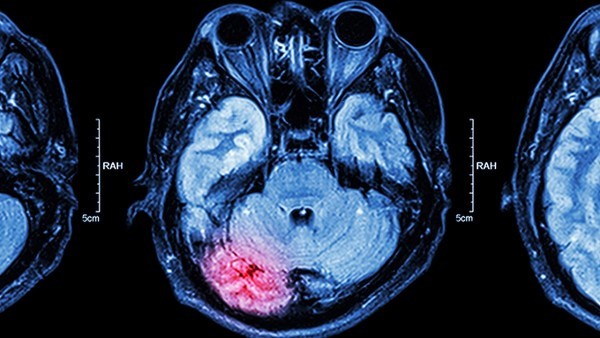

大脑半球肿瘤怎么治

不同大脑半球肿瘤产生的临床表现有差别,不管是哪种症状都会损伤患者健康,所以要积极进行治疗。目前手术治疗是治疗本病最基本的方式,其次可以进行补充治疗,也就是进行放射治疗和化学治疗。

脑干肿瘤有什么症状

脑干肿瘤分为好几种类型,大概有三种,即:中脑肿瘤、桥脑肿瘤、延髓肿瘤等,每一种肿瘤的症状都不同。根据肿瘤的类型不同,患者会出现颅内压增高、眼神经麻痹、肌张力增强、眩晕、共济失调、头昏、头痛、吞咽困难、进食呛咳、讲话鼻音、伸舌不能等症状。